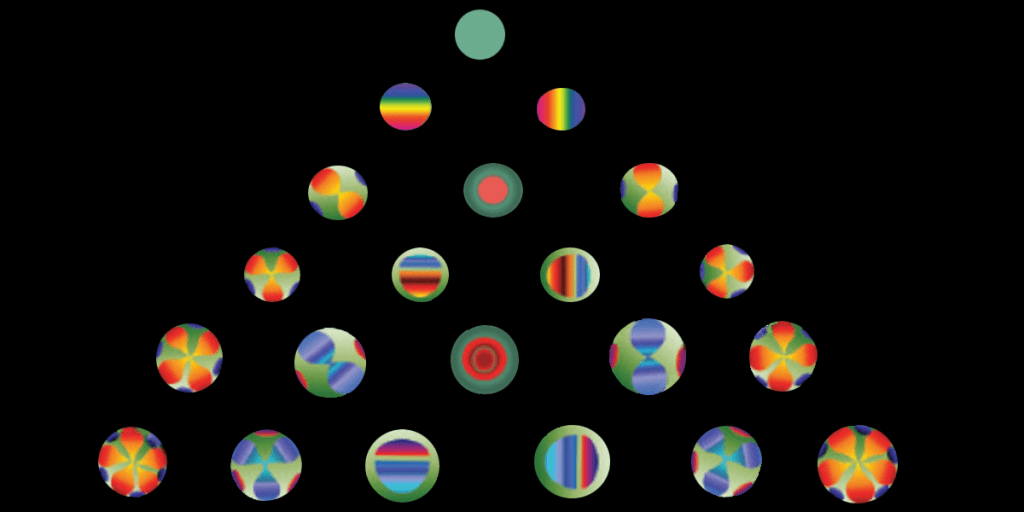

Why do stars sometimes “twinkle” in the sky? Atmospheric turbulence: the light that comes from the star gets distorted by particles in the atmosphere. It is the same with light entering the eye: it passes through the cornea and the lens (the “optics”) and is focussed on the retina (the neurological part) where the light is converted into nerve impulses that are transmitted up into the brain. Imperfections – particularly in the cornea, which is responsible of 80% of the eye’s focusing power – can then distort the light in many different ways. Some wholesale imperfections in the system (like myopia, hyperopia and astigmatism) are quite obvious, and are termed “lower-order aberrations”, whereas others tend to be only noticeable at night, and have terms like “trefoil, coma and spherical aberration”, and are referred to as “higher order aberrations” – HOAs. The more complicated the shape that the light gets distorted into, the higher the order of aberration (Figure 1).

Figure 1. Common aberration shapes created when a “wavefront” of light passes through eyes with imperfect vision. A theoretically perfect eye (top) is represented by an aberration-free flat plane known as a “piston”. Each row further down from the top represents an increasingly “higher order” (i.e. more complex) aberration.

Many clinics have corneal topographers that can also perform a corneal aberration analysis, and they work by determining anterior and posterior corneal elevation data (the shape of the top and bottom of the cornea). This is combined with a technique called ray-tracing, and the resulting data is represented as something called the “Zernike polynomial” – as seen above in Figure 1.